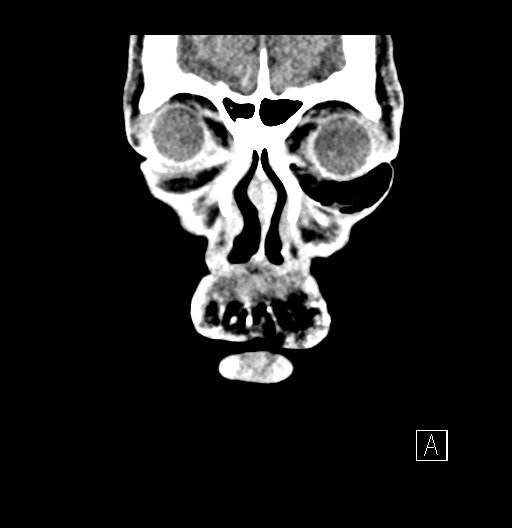

Physical exam showed marked left palpebral subcutaneous crepitus, as well as bulbar and palpebral conjunctival bulging. Visual acuity was normal with intact extraocular movements, and normal pupillary exam. Computed tomography (CT) imaging of the face was obtained and revealed multiple displaced fractures involving the left orbital floor and zygomatic arch associated with moderate periorbital and postseptal extraconal gas, resulting in orbital proptosis.